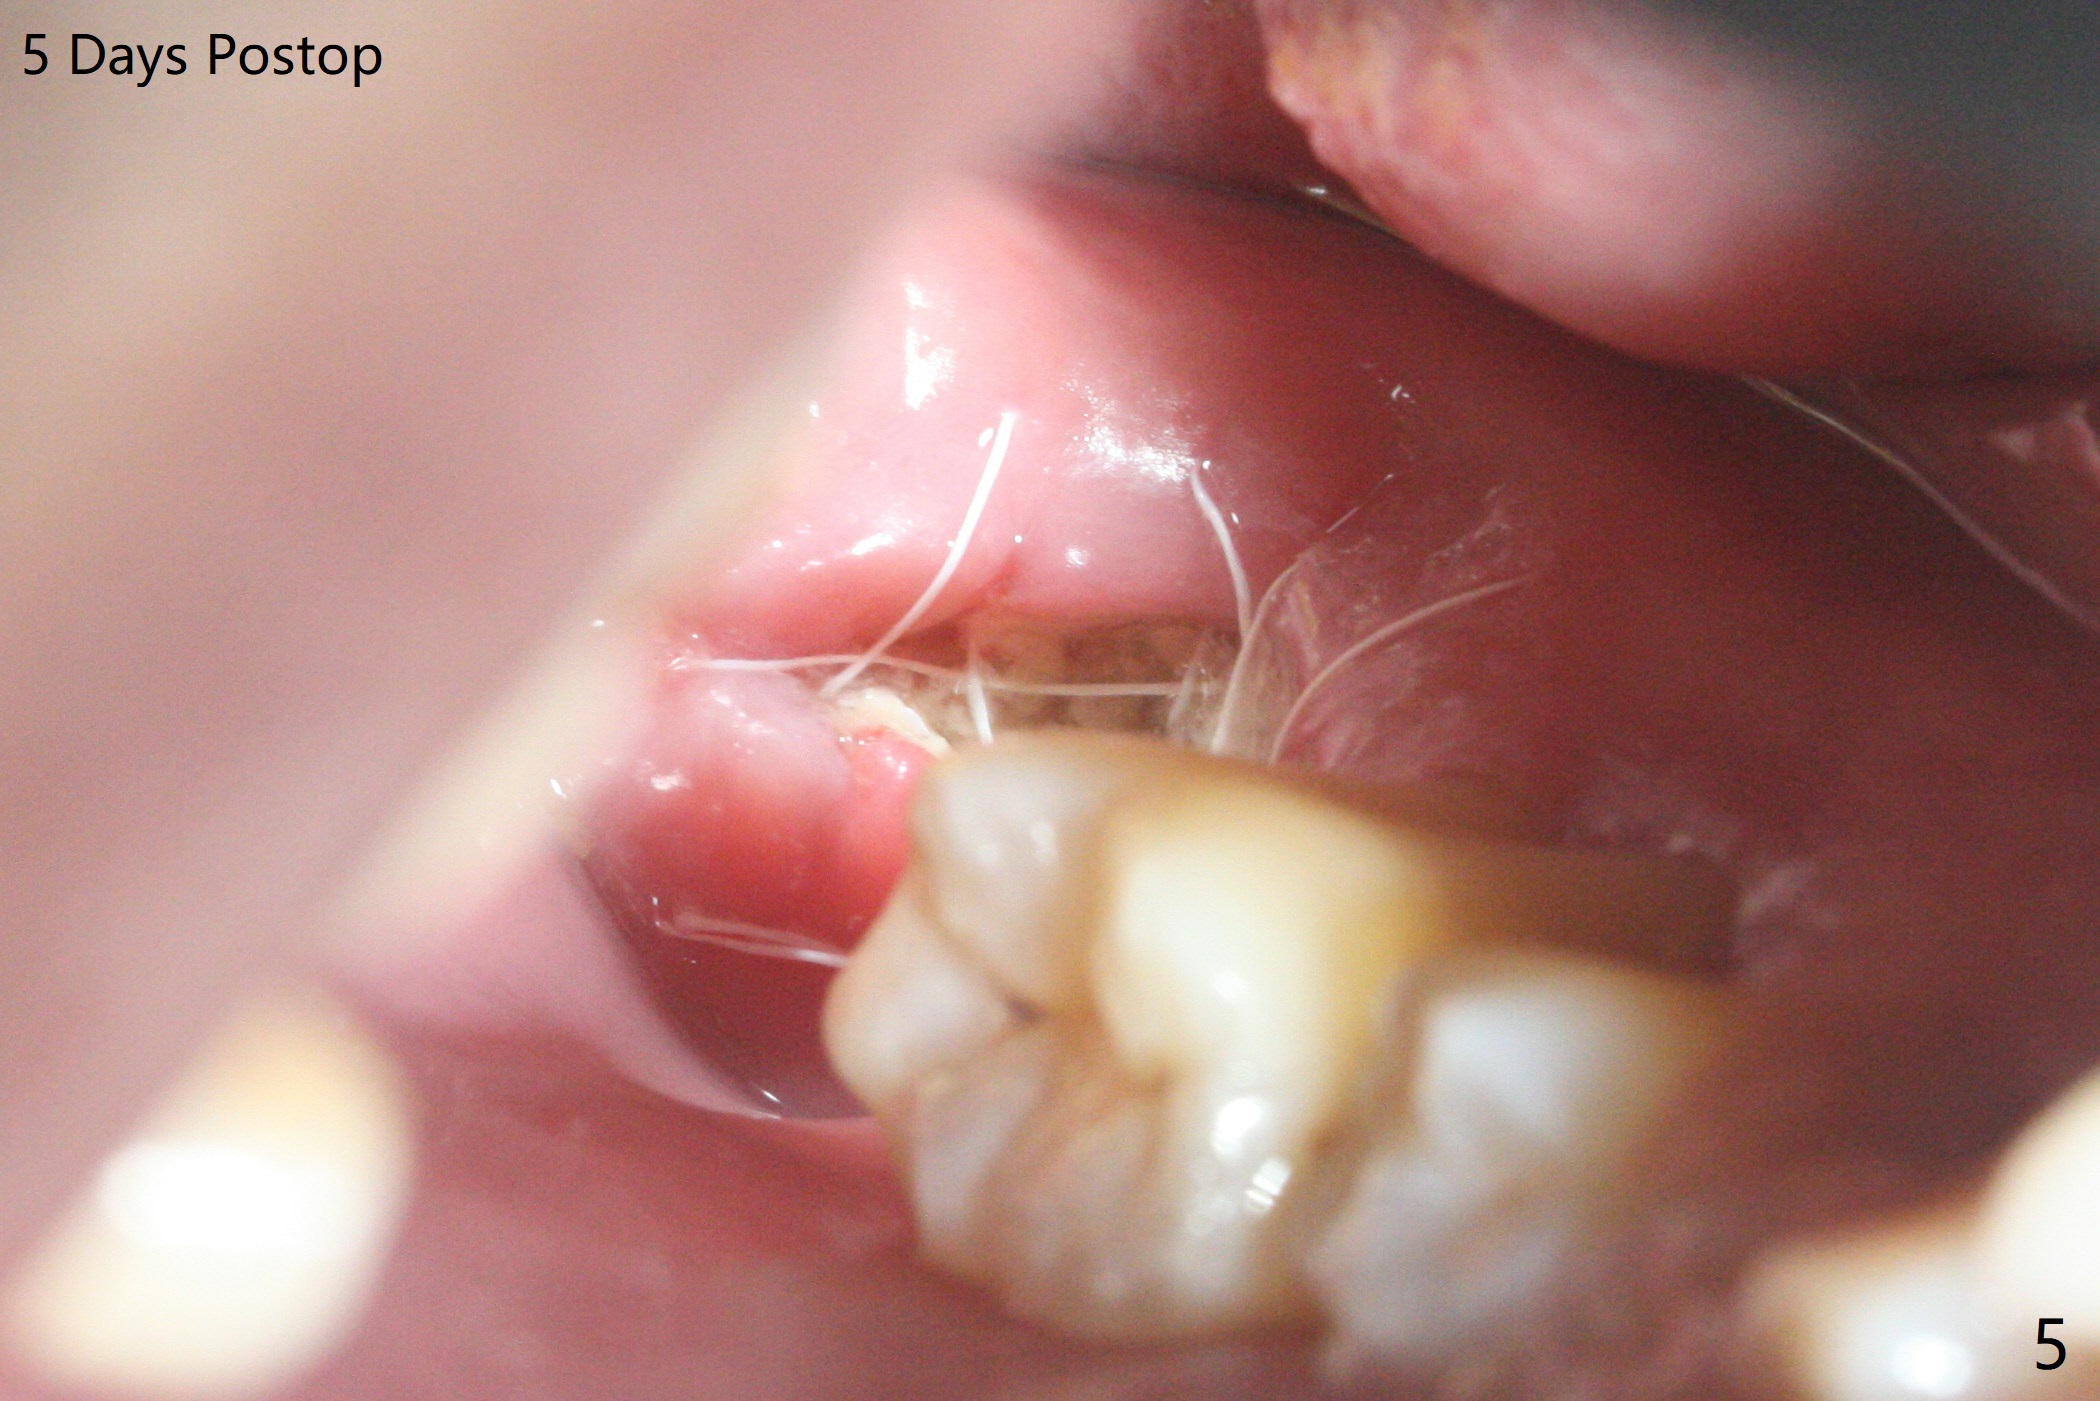

40岁男,牙周炎(图一,4年前拍摄),现在要求拔除31号牙,劝导后同意植骨,问题在于牙根长(图二),可能接近神经(红虚线)。拔牙后,舌侧骨板缺失,不敢大胆在根尖清创,术中拍摄根尖片(图三),牙槽窝根尖接近神经管,最后可能遗留些根尖肉芽组织(图四:*(最好拍摄CT))。粘性骨粉表面覆盖PRF和Cytoplast,使用4-0 PTFE缝线,没有使用牙周敷料,因为后者往往与缝隙粘连,脱落时缝线必须撤除,可能影响不可吸收膜固定。不过这次不可吸收膜术后四天脱落,术后五天骨粉好像丢失不多(图五),可能与粘性骨粉有关。下次需要牙周敷料,牙齿长,敷料固定好。Return to Protect Graft 19 位点保存 Xin Wei, DDS, PhD, MS 1st edition 06/28/2021, last revision 07/09/2021